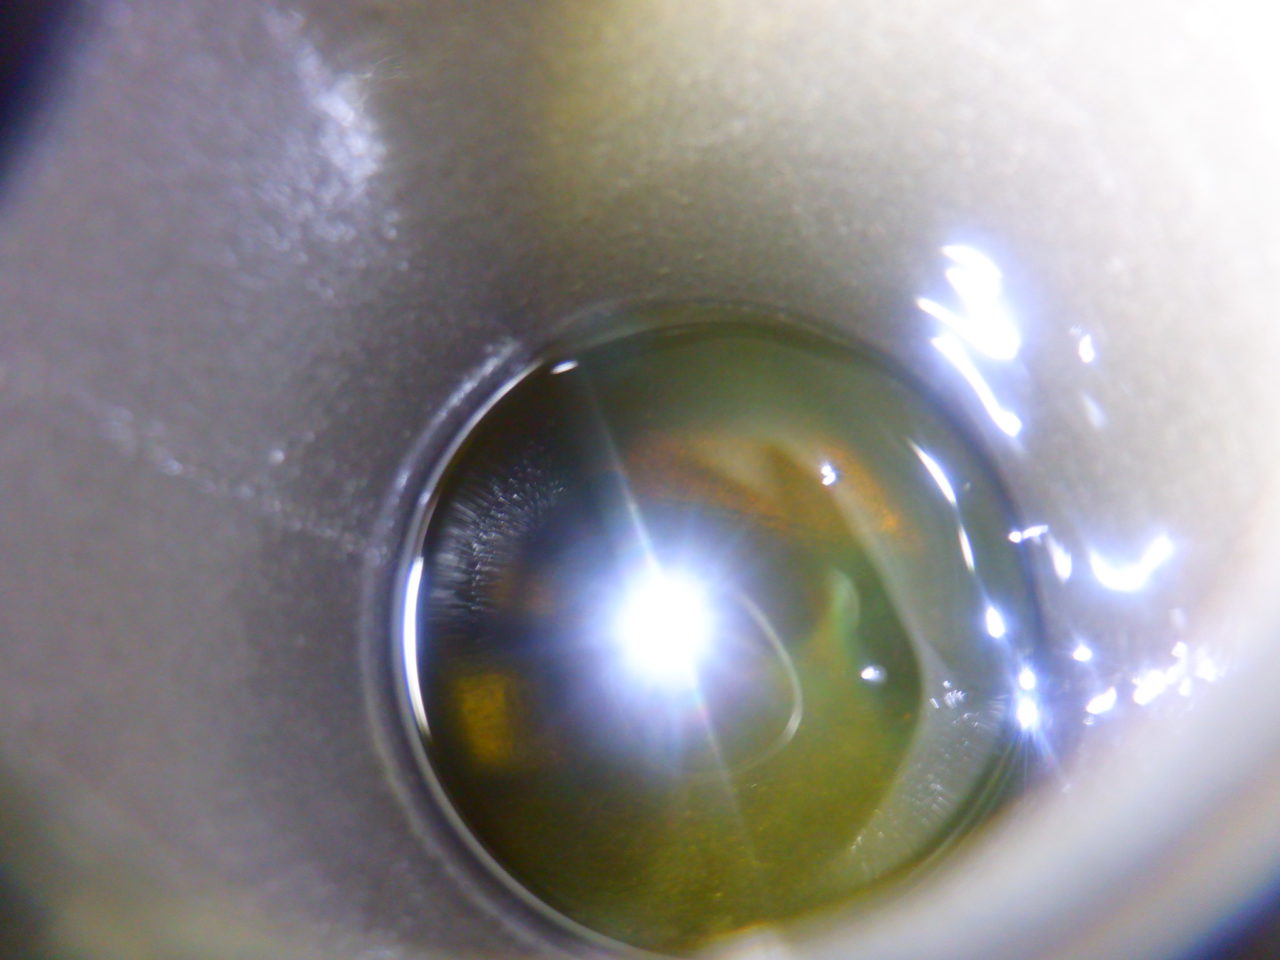

車検のZN6スーパーチャージャーは新品ベルトを取り付けて、トラクションフルードを交換していきます

めちゃくちゃ汚れておりました